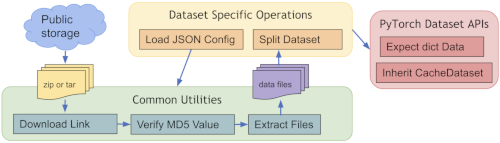

为了快速开始使用公开的数据集(如 MedNIST 和 DecathlonDataset),MONAI 提供了几个开箱即用的函数(例如MedNISTDataset、DecathlonDataset、TciaDataset),其中包括数据下载,解压以及创建dataset(继承了MONAI 的 CacheDataset,训练的时候数据加载的嘎嘎快)。 预定义数据集的常用工作流程: